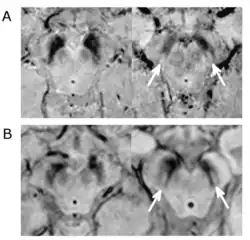

Substantial loss of melanized dopaminergic neurons in the substantia nigra pars compacta (SNpc) is a major characteristic of PD pathogenesis. Many studies have shown that differential prevalence of PD between ethnic groups is due to differences in the number of melanized neurons in the substantia nigra. Most Indians, compared to populations with European origin, have around 40% lower in number of melanized nigral neurons, however, they also tend not to lose these neurons with age. Although Indians do have a lower SNpc volume, this population tends to have a higher neuronal density as well as number of neurons which is hypothesized to be the reason for a lower incidence rate of PD, but this needs to be expanded upon.[5]